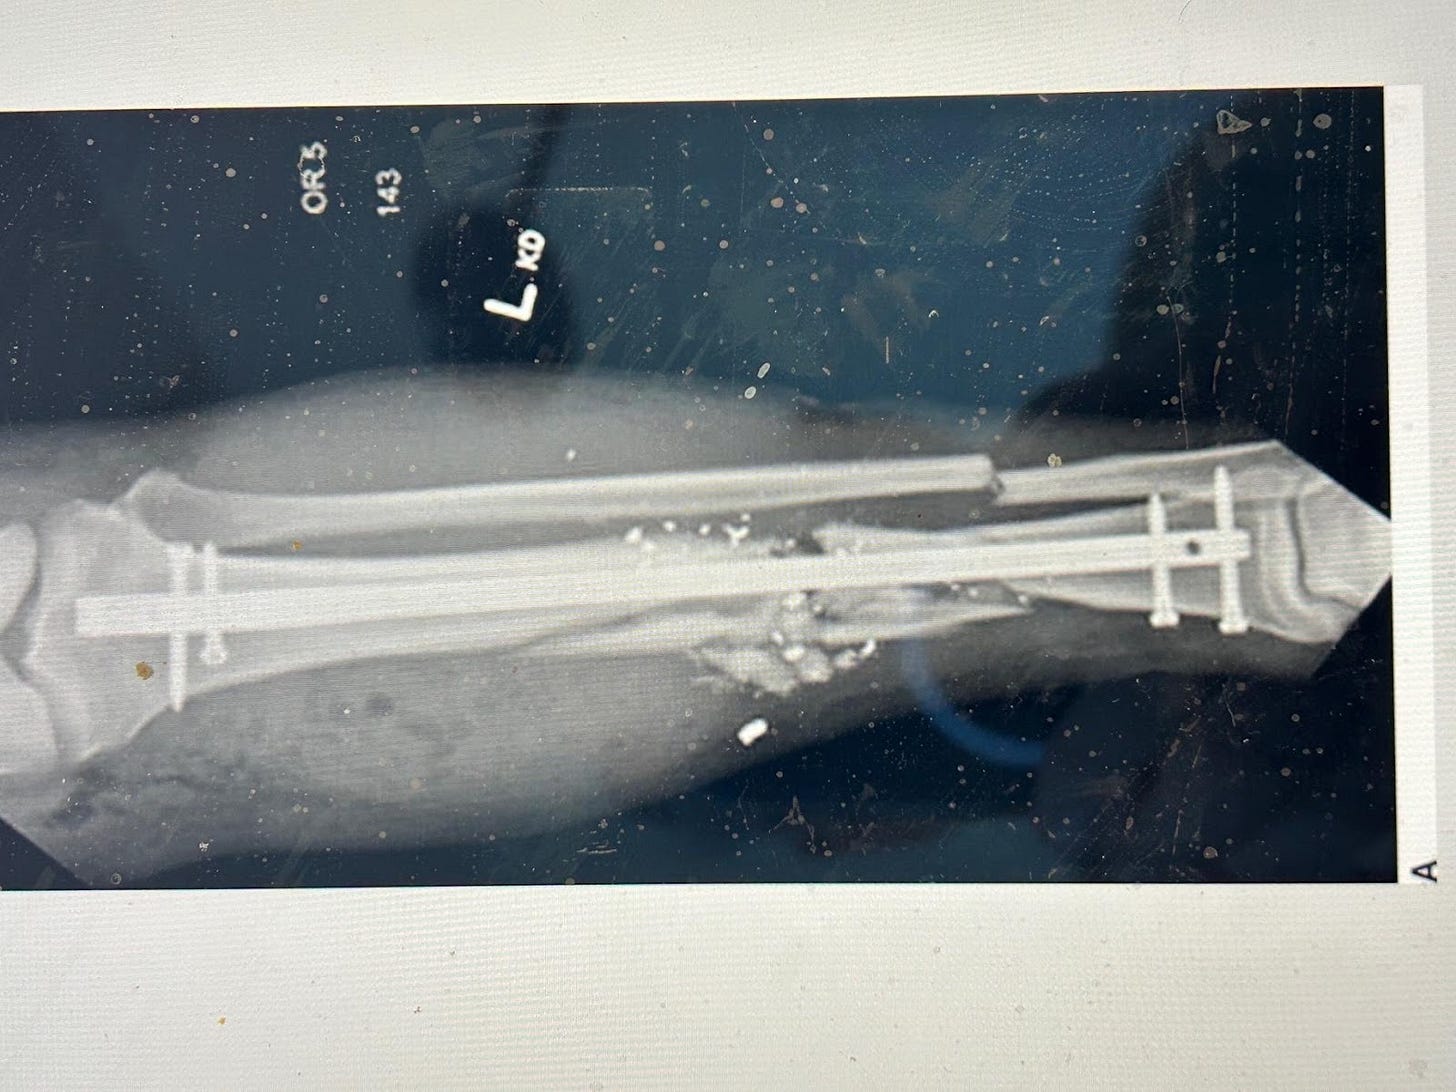

Below is a good method of fixation for a fractured tibia, an internal metal rod, but look at the contamination and small fragments of bone and metal around it. A situation very like Robert’s. This is a better way to manage the fracture than a splint or plaster but there is a big risk of infection around the rod if the wound is wide open.